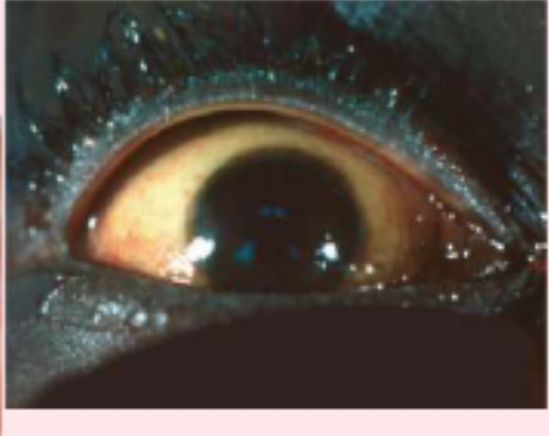

scleral jaundice

corneal scar

which appears grayish white, may be due to inflammation or an old injury.